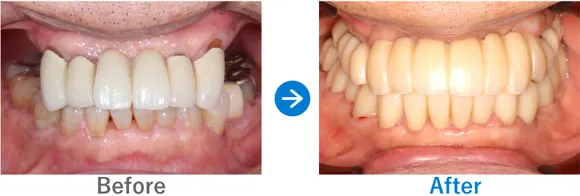

Case3

重度の歯周病を罹患された方。フルマウスインプラント治療直後に仮歯が入り感動されたケース

全顎上下共にブリッジ治療されている。重度の歯周病で歯がグラグラしている。

上下、ALLON4

5,884,000円(上下総額/内訳:上顎オールオン4(ノーベルインプラント4本)、下顎オールオン4(ノーベルインプラント4本)、3Dモデルガイド*、仮歯、セデーション、ボツリヌストキシン注射、3D模型、保証10年)

来院の背景

全体的に重度の歯周病に罹患しており、歯がグラグラしており抜けそうで咬めない、食事ができなく困っていた。インプラントを検討していたが他院で800万円〜900万円と聞いた。デンタルローンを申請。

治療結果

上下のALLON4を実施して治療同日に上下手術を行った。治療後すぐに仮歯が入ったので、とても喜んでいただいた。治療終了。メンテナンス来院継続中。

現在、セルフケアもしっかりされていて、メンテナンスも欠かさず来院していただいているため、インプラントは問題なく使えています。先日、横浜院で10年ぶりくらいにお会いしたのでご挨拶したら、とても喜んでくださりました。あの時インプラントの決断をして良かったと仰っていました。